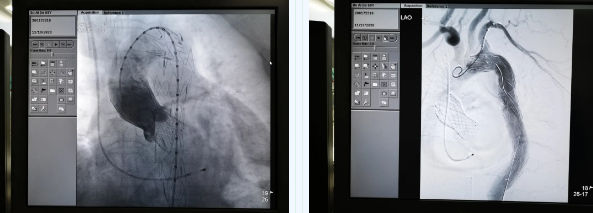

張金洲副院長關(guān)注著手術(shù)的每一個細(xì)節(jié),從建立軌道、跨瓣、釋放瓣膜、支架定位、造影和食道超聲確認(rèn),每一步都緊張而有序地進(jìn)行著。為了最大程度保障病人安全,心臟外科程亮副主任也帶隊建立動靜脈入路,以備緊急體外循環(huán)。經(jīng)過團(tuán)隊每一位成員的密切配合,在近四小時的緊張奮戰(zhàn)之后,“TAVR TEVAR”復(fù)合手術(shù)順利完成;經(jīng)過造影和食道超聲證實(shí):人工主動脈瓣無返流無瓣周漏、冠脈顯影良好,主動脈覆膜支架無內(nèi)漏無移位。